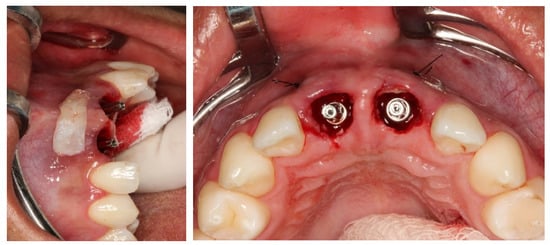

2.5. Surgical Procedures

3. Results

Result and Follow-Up